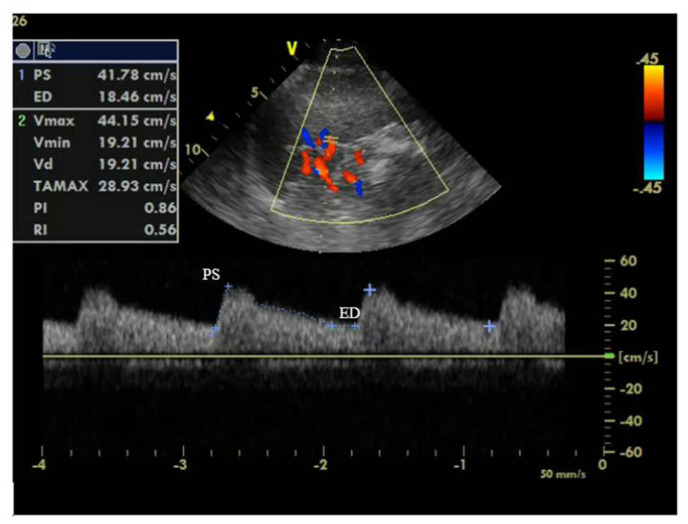

Methods: This was a prospective study that enrolled 100 patients with a diagnosis of ADHF and received intravenous diuretic therapy. Intra-abdominal pressure (IAP), splenic Doppler impedance indices and serum prouroguanylin were measured on admission, 24 h after admission and on discharge. Patients were then divided into 2 groups: those who developed WRF (WRF group), and those who did not (non-WRF group). Worsening renal function was defined as an increase in serum creatinine level ≥0.3 mg/dL above baseline admission value. Intrabdominal pressure was measured transvesically using standard Foley catheter. Splenic Doppler impedance indices (resistivity and pulsatility indices) were measured using splenic Doppler ultrasound.

Results: Among recruited patients (age: 54.73 ± 13.1 years, 72% are male), there was a significant decline in IAP (6.67 mmHg vs 8.36 mmHg, p = 0.001) and significant rise in splenic resistivity index (0.69 vs 0.67, p = 0.002) before discharge compared to admission values. The median level of serum prouroguanylin before discharge showed significant decline compared to admission level (29.2 vs 34.6 ng/l, p = 0.006). WRF developed in 37 (37%) patients. Independent predictors of WRF during hospitalization were high splenic arterial resistivity index 24 h after admission, high intra-abdominal pressure (≥8 mmHg) 24 h after admission, and low LVEF on admission.

Conclusion: In ADHF patients receiving diuretic therapy, transvesical measurement of intra-abdominal pressure and splenic resistivity index by splenic Doppler early after admission can help to identify patients at increased risk of WRF near discharge.